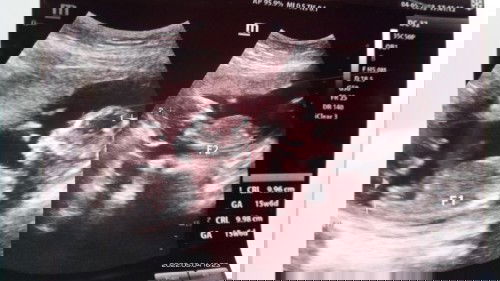

Kembar identik

Ass, sya ingin membagi cerita, usia kehamilan sy masuk 7 bulan, sy mengndung 2 bayi kembar identik, alhmdulillh posisi keplanya sudah d bawah semua, apakah kalau SDH posisi kplaa janin d bwa akan brputr lagi? Atau TDK lama lagi akan lahir, ? Mohon saranya yg brpglmn, mohon doanya ya bunda2, niat sy mau melahirkan secara normal bunda2, anak pertamaku juga kembar lhirnya normal,, kmbr identik jg,mohon doanya yaaaa ,terimah ksih😀